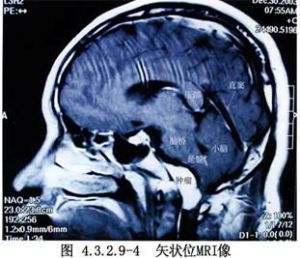

枕骨大孔區的腫瘤以腦膜瘤多見,神經鞘瘤次之,腦膜瘤常發生於枕骨大孔區環竇附近,部位多靠近側面或偏向前或偏向後。其供血主要來源於腫瘤基底的腦膜動脈,也有一部分來自椎動脈與小腦下後動脈分支。腫瘤長大可使第9、10、11、12顱神經受累,同時也可壓迫延髓與上段頸髓,發生球麻痹與錐體束徵等症狀。神經鞘瘤主要來自頸神經根,通過枕骨大孔向上長入顱後窩,尚有舌咽神經瘤與舌下神經瘤(圖4.3.2.9-1~4.3.2.9-5)。

1.術前必須有正確的定位診斷。近年來由於影像檢查技術的進步,CT、MRI、DSA等臨牀應用日益廣泛。對病變的部位及與周圍結構的關係術前應詳加分析,以便選擇合適的手術入路,爭取獲得最好的顯露,儘可能地避開顱內重要結構,增加手術的安全性和爭取良好的效果。